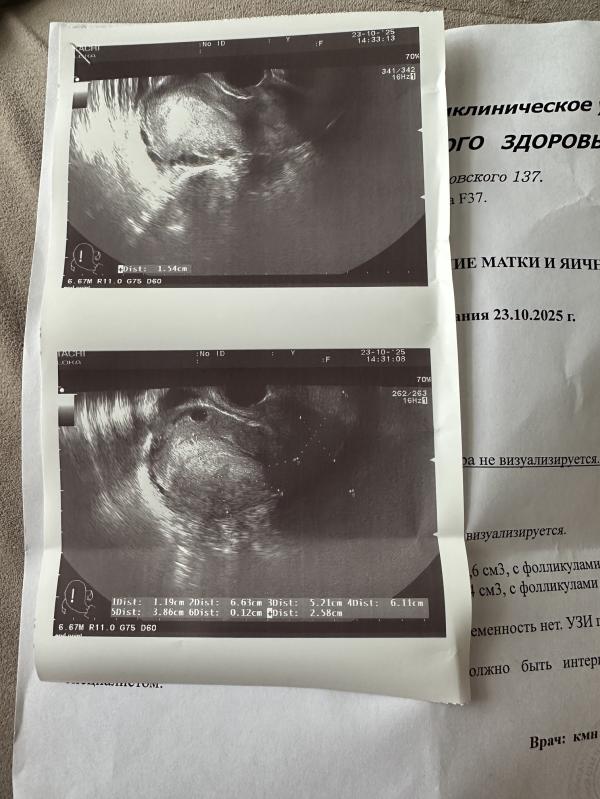

20 дпп решила сходить на узи, плодного яйца нет, сдала хгч. Купила тест какой то бракованный, полоски поярчали сразу же, многвенно. Моя поярчала быстрее чем контрольная, господи что происходит( сказала что подозрение на внематочную, в левой трубе( эндометрий маленький, потом сказала 15-16 мм.

Какое-то очень странное описание узи. Желаю, чтоб у вас все было хорошо и грамотный врач нашел пя в нужном месте!

Вы конечно извините но верить в лучшее на 20 дпп если в матке нет пя тут нет смысла , надо искать срочно хорошего специалиста узи что бы искали в трубах его

Тут два варианта либо врач который делал узи идиот слепой и реально не смог увидеть либо это вб. Найдите экспертное узи на хорошем аппарате и бегите туда , прям бегите потому что вб это опасно .